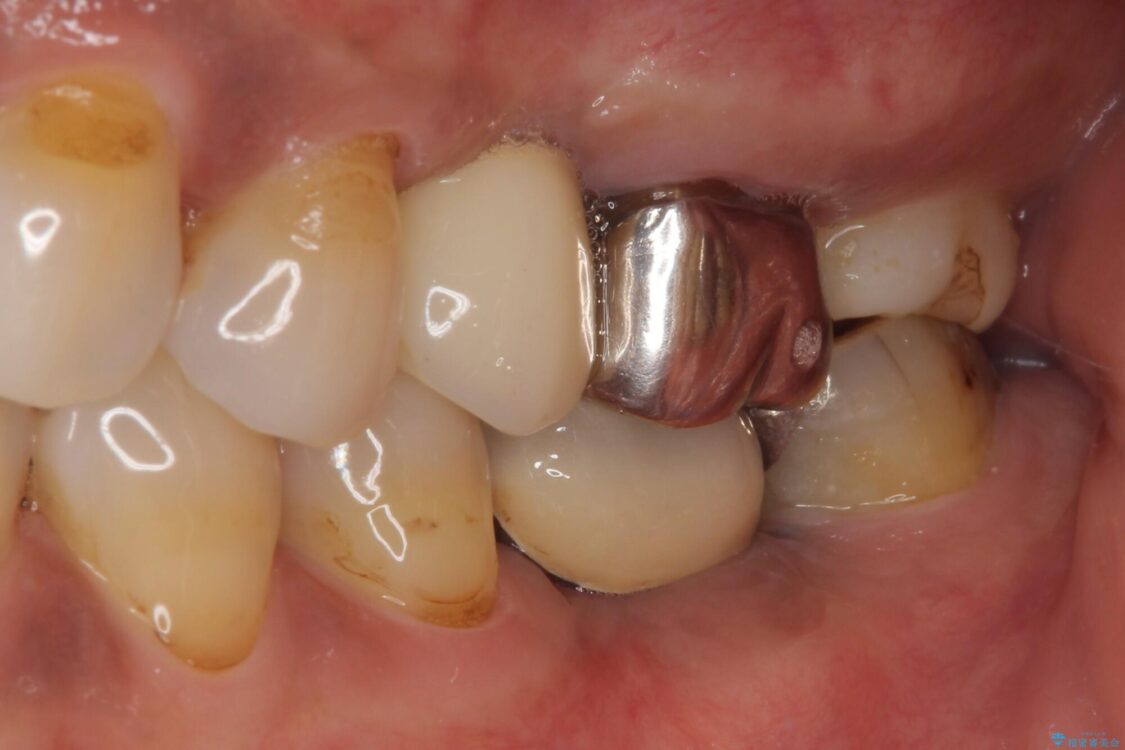

治療前

• しみる奥歯 オールセラミッククラウンによる補綴治療 治療前画像

銀歯の装着されている奥歯がしみるとのことで来院された患者様です。

銀歯周辺の歯が欠けており、むし歯も進行している状態であったので、オールセラミッククラウンにて補綴治療を行うこととしました。